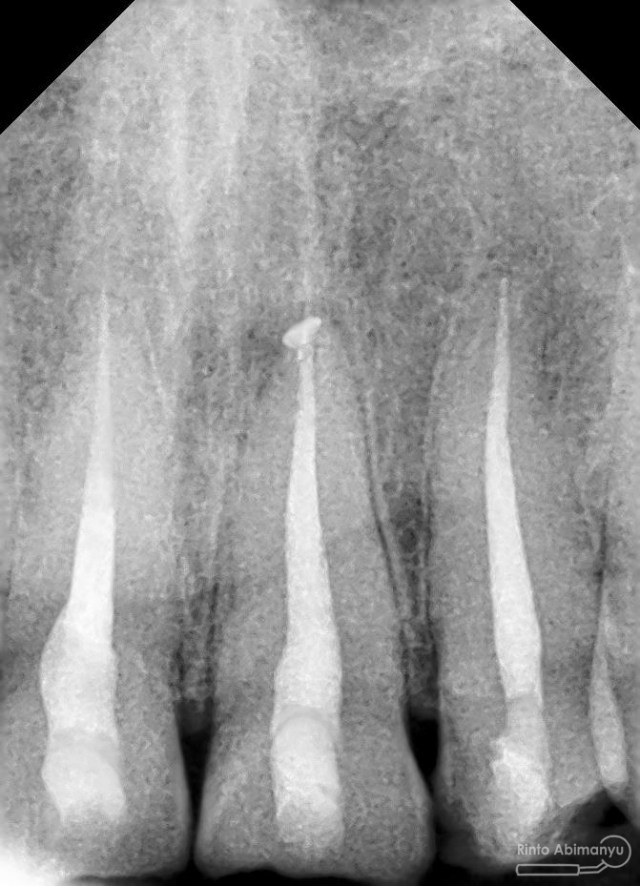

Foto radiografis trial guttap gigi 22

Nah dari foto ronsen ini juga saya melakukan evaluasi hasil pengisian pada gigi 11 21 nya… alhamdulillah pengisian yang kemarin terlihat sepanjang kerja dan padat serta rapat… Pada gigi 22 nya pun pengepasan guttap terlihat sudah sepanjang kerja…

Foto radiografis selesai perawatan saluran akar pada semua gigi